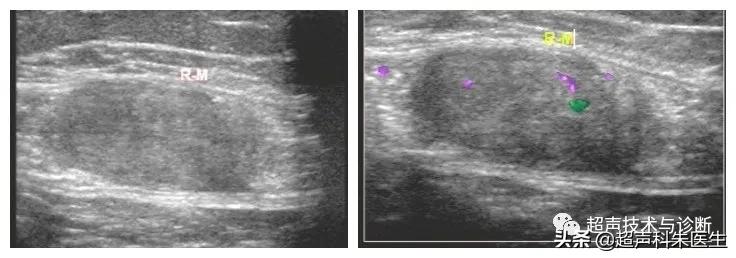

高频探头显示包块与腹直肌的细节关系

高频探头显示包块内部回声细节

超声所见:下腹部腹膜外探及一低回声团块,大小12.4*6.9*9.0cm,边界清楚,内部回声不均质,内见散在点状强回声及小片状无回声区,包块与腹直肌分界不清,CDFI观察:其内可见少量血流信号。